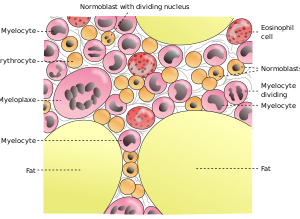

النخاع

العظام الطويلة تكون متصلة بالعضلات الهيكلية بالأوتار. ترتيط العظام بعضها ببعض بواسطة المفاصل والتي ترتبط بلأربطة. يوجد نخاع العظم الاحمر في المادة الخلوية للعظم الاسفنجي، مما يسمح للعظم من انتاج خلايا الدم الحمراء. وأيضاً يوجد نخاع العظم في ساق العظام، ويقوم بتوليد خلايا الدم البيضاء.